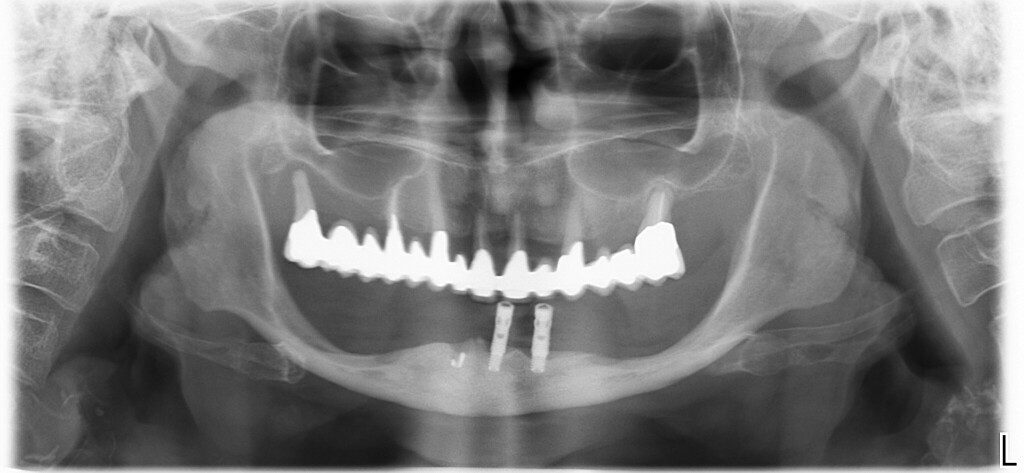

La paziente ritratta in questa panoramica arrivò da me più di tre anni fa.

lamentava il fatto che la situazione era ormai insostenibile ed era convinta di non poter mettere impianti perché la situazione della mandibola era troppo compromessa.

Chiacchierando un po’ venne fuori che non uno, ma molti colleghi avevano detto alla signora che non c’era nulla da fare.

Se fino a quel punto non era saltata fuori una soluzione significa che i colleghi che l’avevano vista in precedenza erano veramente convinti che non ci fosse nulla da fare, o forse, che il caso fosse troppo complesso e incasinato.

Ma sono convinto che questa fosse caratteristica comune di tutti i colleghi che in precedenza avevano valutato il caso. Di scuro il precedente dentista che le aveva messo quegli impianti che vedi tempo prima metteva impianti da molti anni. Sicuramente la signora aveva chiesto pareri a validi professionisti, visto anche il mestiere del figlio. Eppure tutti avevano rimbalzato il caso.